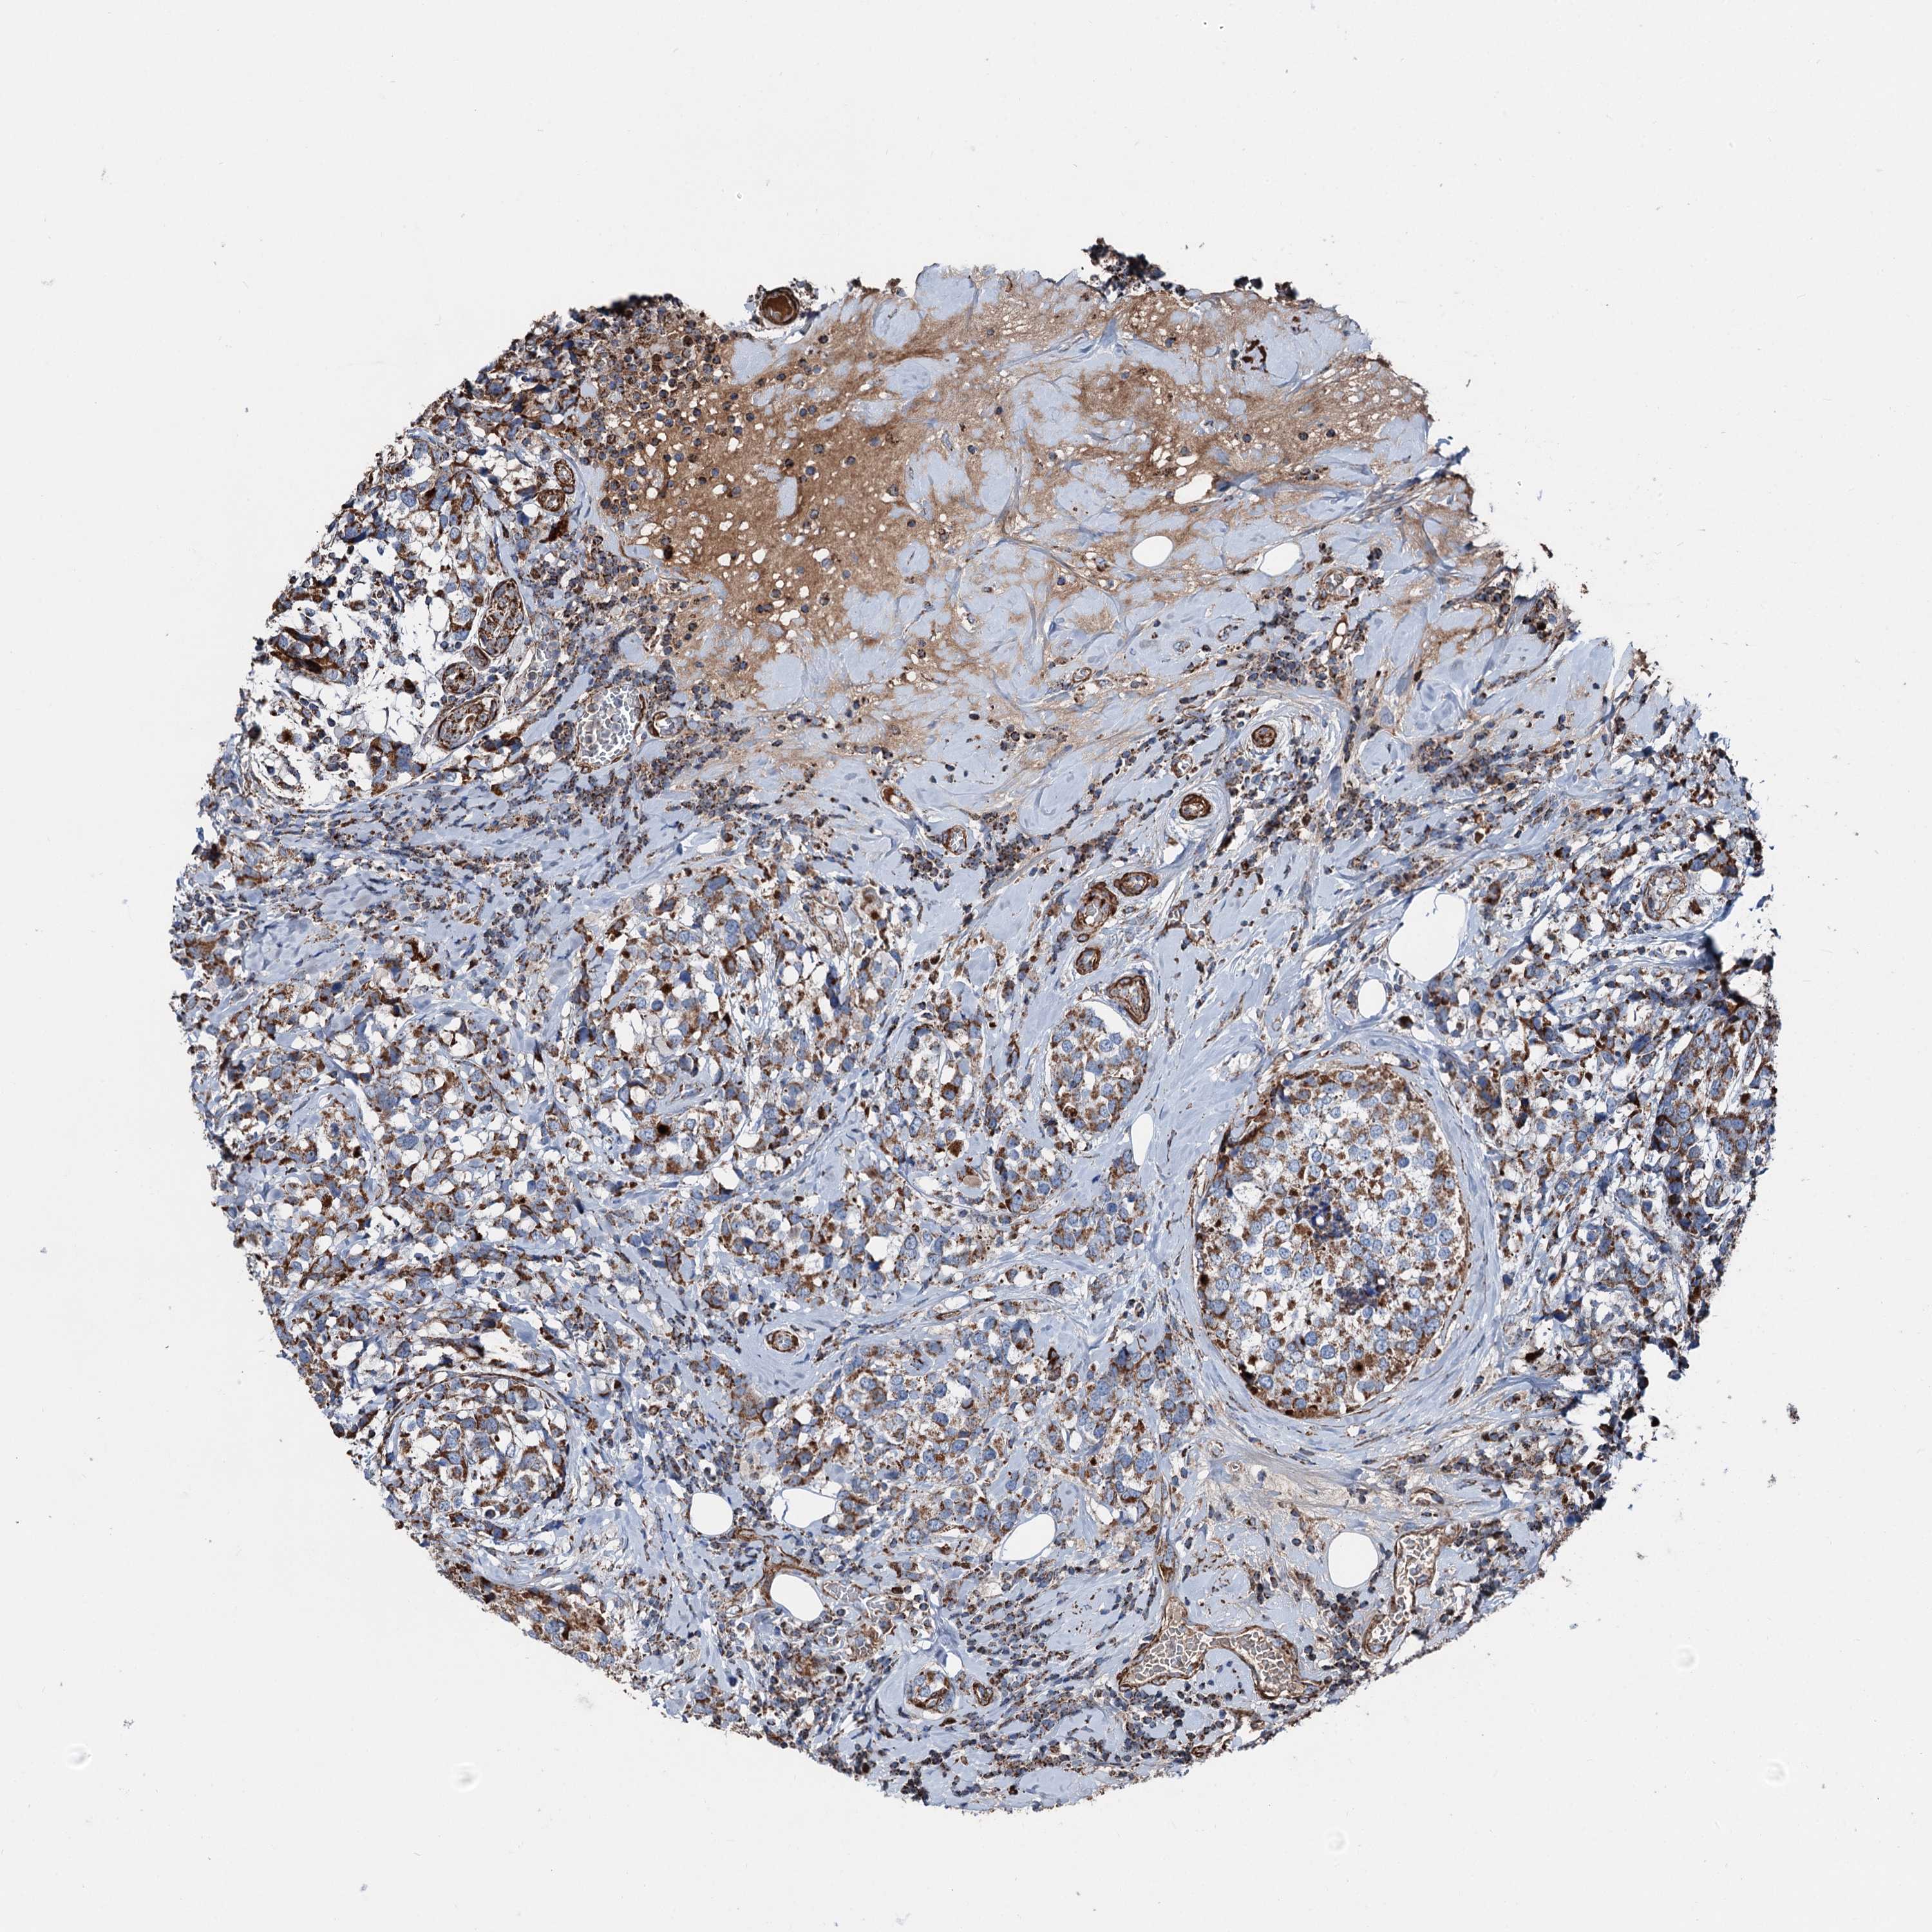

BRCA TCGA BRCA VALIDATION PROTEIN EXPRESSION